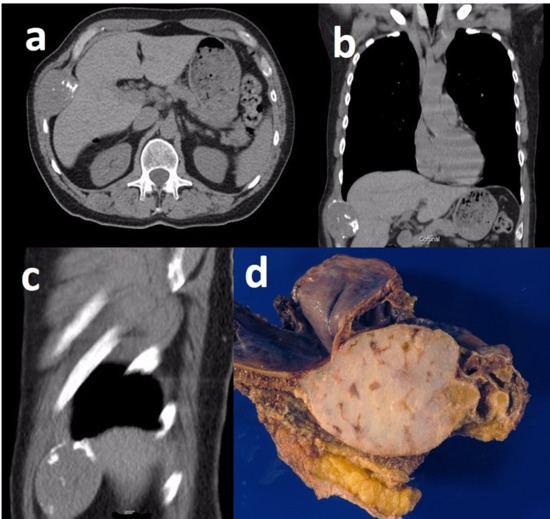

Grade 1 and 2 Chondrosarcomas of the Chest Wall: CT Imaging Features and Review of the Literature

3. Results

4. Discussion